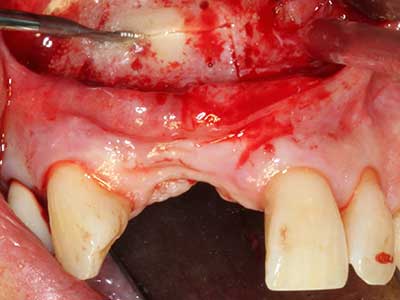

Fig. 18: Preparation of a cortical cover with the piezo bone saw (Piezomed, W&H).

Fig. 19: Surgical site after neurolysis and removal of osteoma.

Fig. 20: The removed bone cover is re-adapted and fixed with an osteosynthesis screw (KLS Martin, Tuttlingen).